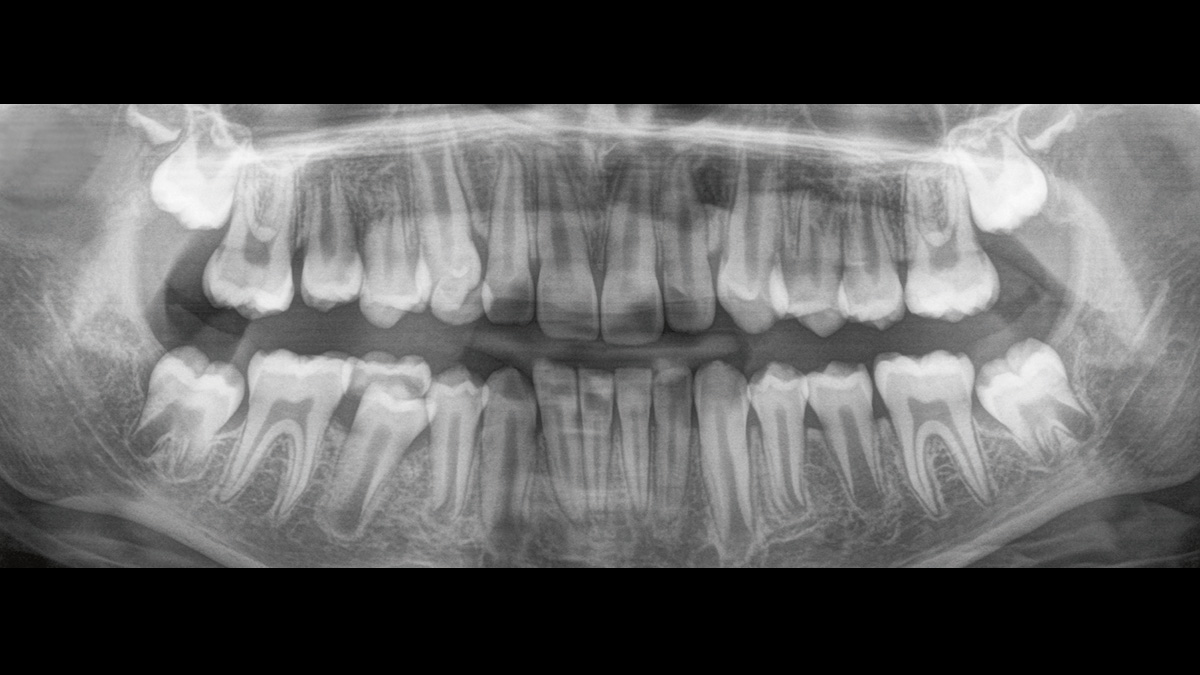

Der Direct Conversion Sensor erfüllt besonders hohe Standards für die 2D-Bildgebung

Der Autofokus erzeugt aus mehreren tausend Einzelbildern automatisch eine beeindruckende scharfe Panorama-Röntgenaufnahme

Der Direct Conversion Sensor (DCS) hat den Standard der Panorama-Bildgebung neu definiert. Röntgenstrahlen werden direkt in elektrische Signale umgewandelt – im Gegensatz zu herkömmlichen Systemen gibt es keinen Signalverlust durch Lichtumwandlung, was eine verbesserte Bildgebung ermöglicht. Das Ergebnis sind Bilder mit einer sehr hohen Schärfe, selbst bei niedriger Dosis.

Eine Röntgenaufnahme muss sofort diagnostizierbar sein. Der Autofokus hilft dabei erheblich. Orthophos SL erfasst mehrere tausend Einzelbilder in einem Zyklus und erkennt automatisch scharfe Bereiche, um ein gleichmäßig scharfes Gesamtbild zu erzeugen. Der intelligente Autofokus erfordert keine manuellen Arbeitsschritte vor und nach der Erfassung.